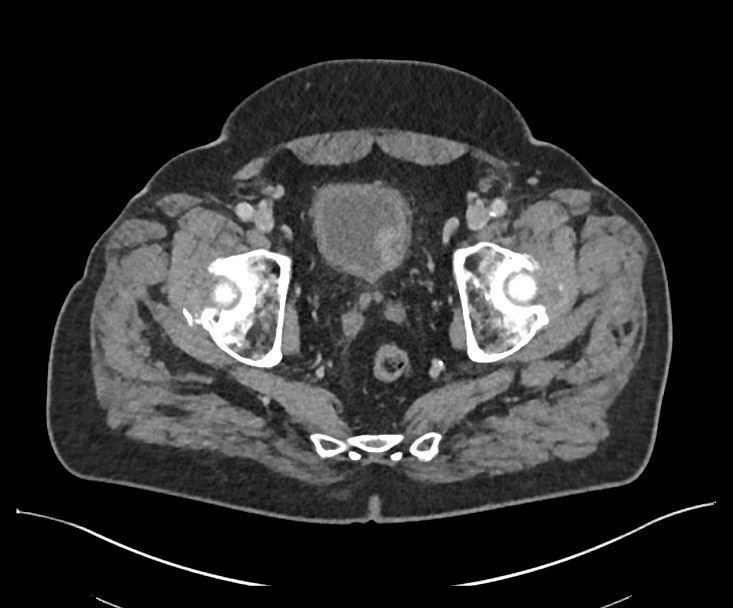

Le diagnostic retenu est une infection urinaire compliquée, associée à une tumeur vésicale découverte fortuitement. Le bilan réalisé par la suite révèle un carcinome urothélial non invasif de bas grade.

Image proposée par l'Hôpital de la Tour.